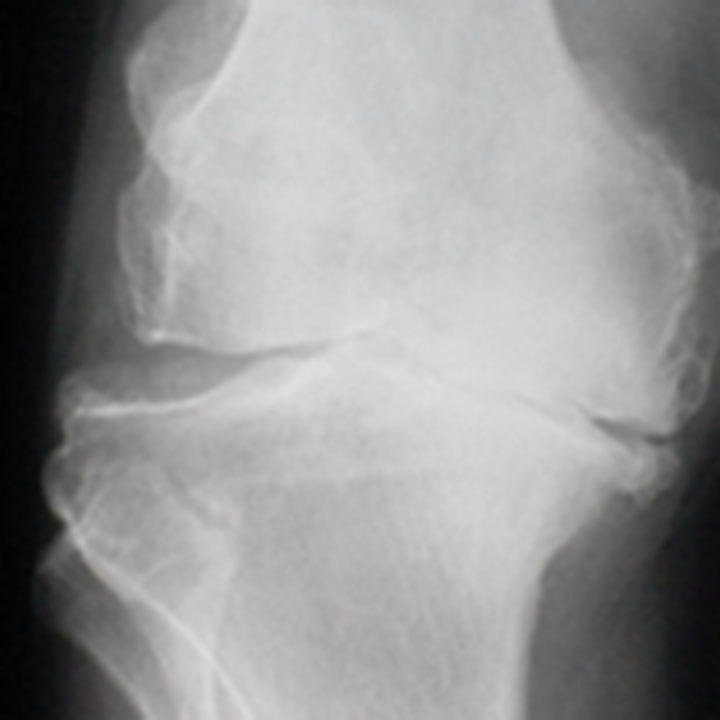

Hvad er slidgigt i knæet?

Slidgigt er den mest udbredte ledsygdom, der rammer stort set alle med alderen. Otte ud af ti har slidgigt, når de har passeret de 50 år. Slidgigt opstår, når brusken mellem knoglerne eftrhånden nedbrydes, og det er den mest almindelige årsag til, at der er behov for at indsætte en knæprotese.

Symptomer på slidgigt i knæ

De første symptomer er typisk smerter ved igangsætning, ømhed efter belastning og hævelse. Ved svær slidgigt opstår der ofte hvilesmerter, nedsat bevægelighed og måske fejlstilling i ledde.